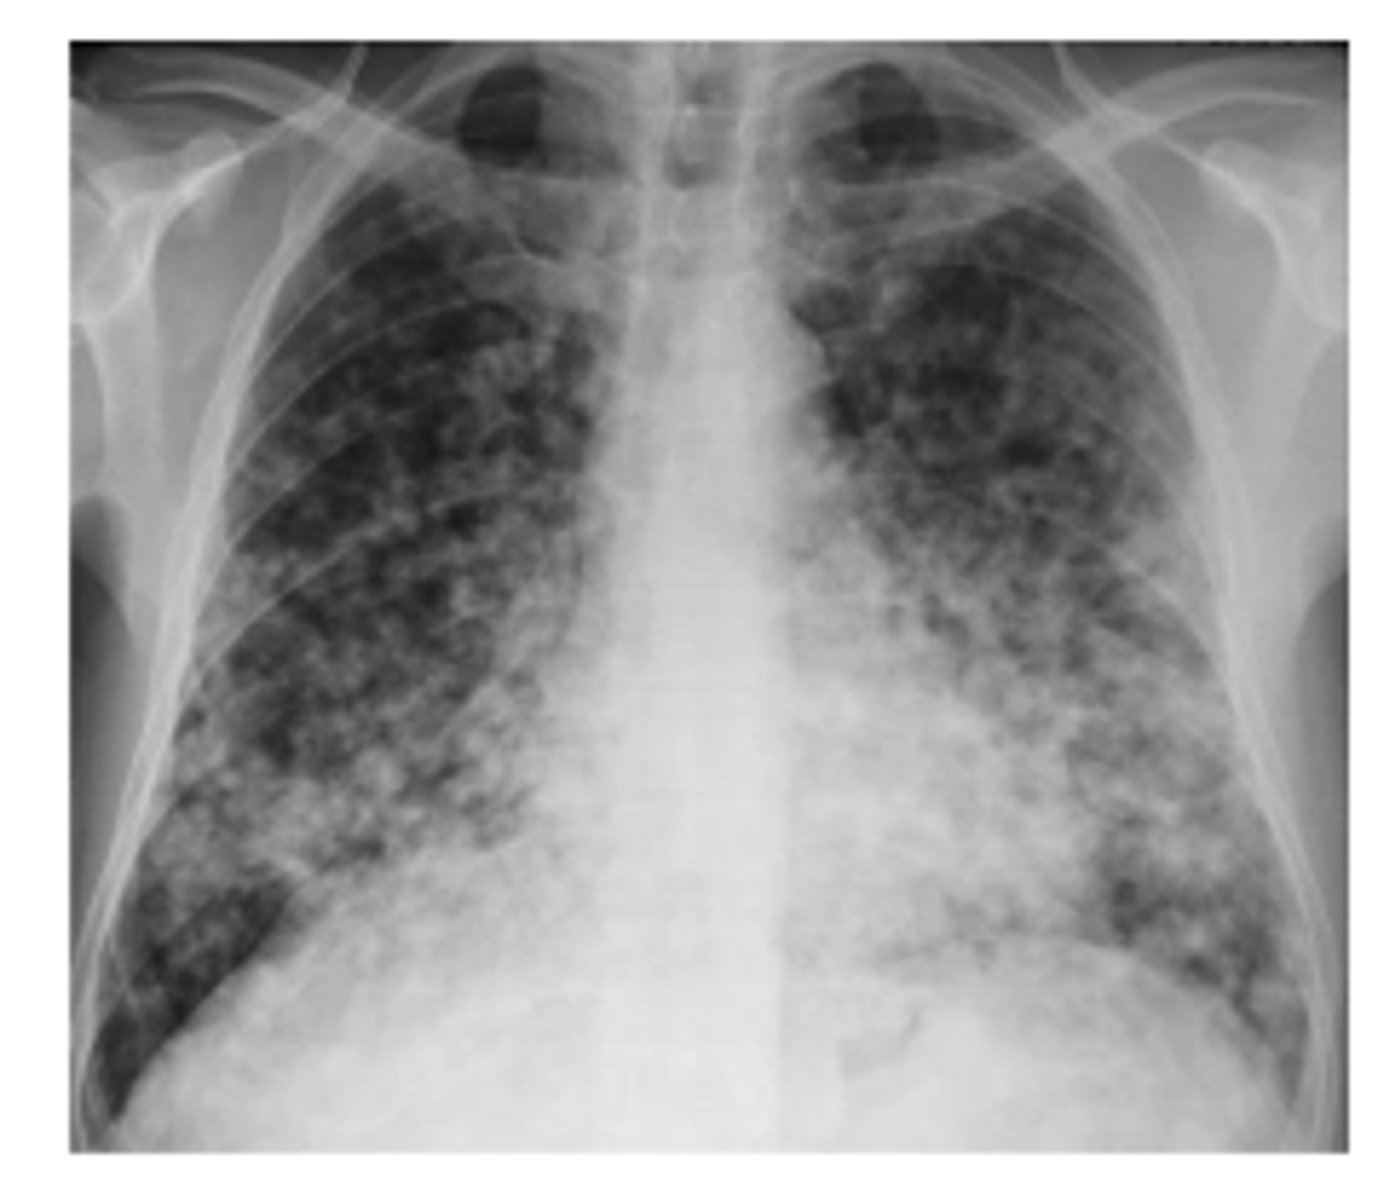

What x-ray findings indicate atypical pneumonias caused by mycoplasma, viruses or pneumocystis? Most common pathogen

Pneumonias that are interstitial and symmetrically diffuse in both lungs

Path: mycoplasma

<p>Pneumonias that are interstitial and symmetrically diffuse in both lungs</p><p>Path: mycoplasma</p>

What is the pattern on the image of the back of the card?

Cystic PJP - PA chest radiograph shows diffuse bilateral reticulonodular interstitial infiltrates

<p>Cystic PJP - PA chest radiograph shows diffuse bilateral reticulonodular interstitial infiltrates</p>